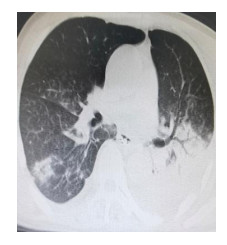

入院第16日(9月22日)患者抽搐较前好转,双上肢抽搐为主,偶有四肢短暂抽搐,心率血压波动仍大,出现肺部坠积性炎症(图 3),白细胞、超敏C反应蛋白及降钙素原均增高,细菌学培养肺炎克雷伯杆菌,根据药敏调整抗生素:特治星4.5 g每6 h一次、万古霉素1 g每12 h一次。同时联系麻醉科使用脑电双频指数(bispectral index, BIS)监测,指导镇静药物使用。

| 图 3 入院第16日肺部CT |